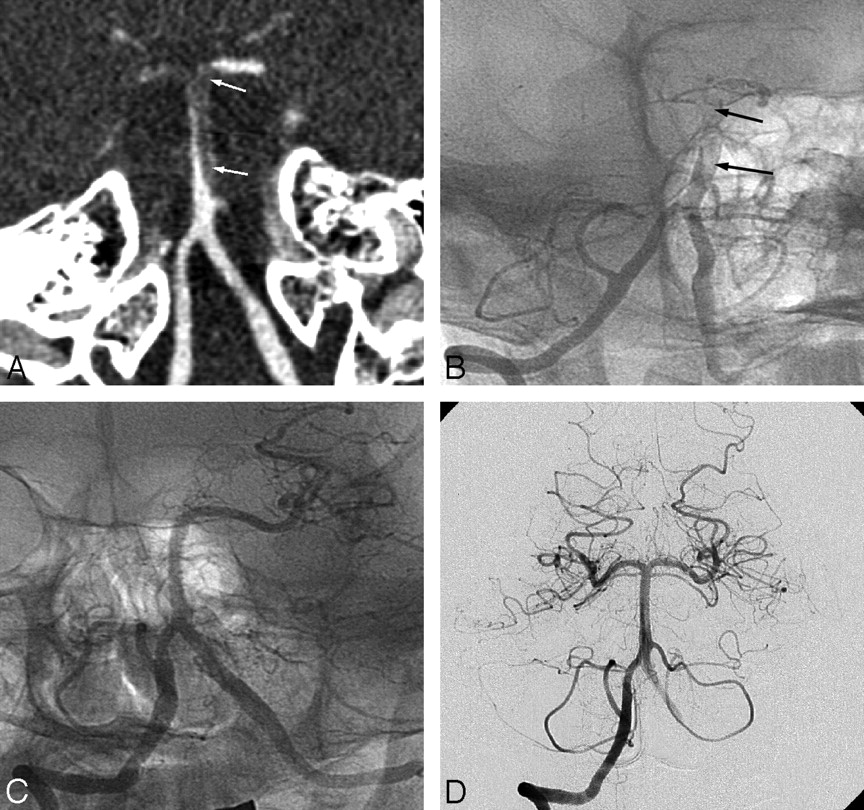

Of the 11 patients with unruptured basilar artery dissection, 2 were initially treated by stent placement. One patient was treated by emergency stent placement for progressive deterioration of consciousness at presentation and near-occlusion of the basilar artery on angiography and completely recovered (Fig 1). The other patient presented with stem compression by a growing pseudoaneurysm 3 years after initial presentation of brain stem infarct (Fig 2). He was treated by double-overlapping stent placement and also completely recovered.

A 30-year-old man presenting with signs of stem compression 3 years after initial presentation of brain stem infarction. A, Initial MR angiogram reveals focal asymmetric dilation in the distal basilar artery. B, CT angiogram 3 years after initial MR imaging as a result of brain stem compression. A large asymmetric pseudoaneurysm is demonstrated in the same location. C, Vertebral angiogram in lateral projection after overlapping double-stent deployment shows flow redirection through the stent and the basilar artery with stasis of contrast media in the pseudoaneurysmal sac (arrows). D and E, A 4-month follow-up vertebral artery angiogram (D) and right internal carotid artery angiogram (E) reveal occlusion of the basilar artery and hypertrophied right posterior communicating artery (arrow), which supplies the distal basilar artery and its branches.

All of the 10 surviving patients treated with the endovascular method underwent follow-up conventional angiography at a mean of 9 months (range, 3–18 months). In 8 of these 10 patients, follow-up angiograms revealed complete resolution of the dilation or stenosis with reconstruction of the basilar artery. In 1 patient who was treated by double stents with coiling for a ruptured basilar artery dissection, a 9-month follow-up angiogram revealed minimal contrast media filling outside the stent (Fig 3). In the other patient who was treated by double-stent placement, a 4-month follow-up angiogram revealed in-stent occlusion of the basilar artery and a hypertrophied right posterior communicating artery that sufficiently supplied the upper basilar artery and its branches (Fig 2). This patient did not have any ischemic complications and completely recovered.